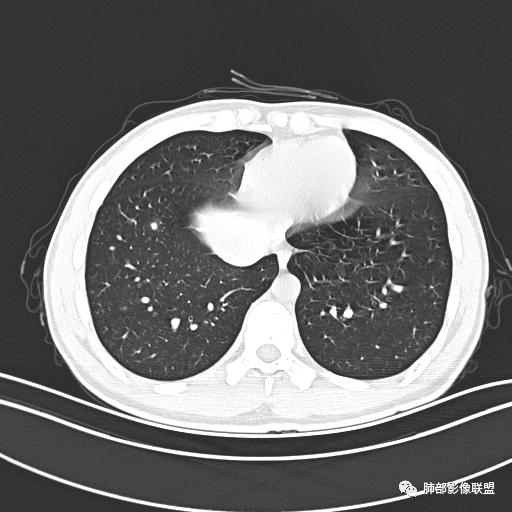

男,19岁

主  诉:发热、全身皮疹2天。

现病史:患者源于2天前受凉后出现发热,最高体温为38.5℃,且颜面部出现少量皮疹,无鼻塞、流涕、咳嗽、咳痰,未在意而未作特殊处理,次日全身皮疹逐渐增多至全身,伴轻度瘙痒,在当地卫生所给予抗病毒、抗感染治疗(具体用药不详)体温有所下降,但皮疹无明显消退,无腹痛、头痛,食欲无明显减退,为进一步诊治,遂于今日急来我院求治,患者目前精神尚可,体力正常,食欲正常,睡眠正常,体重无明显变化,大便正常,排尿正常。

小强:青年,发热,皮疹;双肺散在结节,周围磨玻璃,点晕征,疱疹病毒感染,鉴别荚膜组织胞浆菌,结核。 大雄:青年,急性起病,发热伴全身皮疹2天,抗病毒治疗体温有下降。双肺随机分布大小不等类圆结节,“点晕征”。考虑水痘-疱疹病毒(VZV)血播询问接触史,查体皮疹分布以及形态基本可诊断。 王开金江津中心医院呼吸科:青年男性,起病急,病程短,以发热,皮疹为首发症状,感染指标以单核细胞升高为主,胸部ct双肺多发结界,周围有晕,点晕表现,随机分布,同意於老师意见,水痘疱疹病毒血流感染累及肺。 王秀仙:双肺多发大小不等结节,周围有晕,边缘模糊,呈点晕征表现。青年,急性起病,发热伴全身皮疹2天,抗病毒治疗体温有下降。考虑疱疹病毒。鉴别荚膜组织胞浆菌。 傅昌瑜:19岁男性,发热、全身皮疹2天,单核细胞增高,双肺多发结节,结节边缘见边界不清磨玻璃影。点晕征+发热、全身皮疹+单核细胞增高——考虑水痘-带状疱疹病毒肺炎。 一切∮随缘:年轻男性,发热,皮疹两天,实验室,CRP,PCT增高,影像:双肺多发散在磨玻璃结节,边界欠清,大小不等,呈点晕征改变,以血管束周围分布为主,局部血管束略增粗,其它无明显改变,考虑:1:病毒性肺炎(水痘疱疹病毒?不知道皮肤有无改变)2:真菌(组织胞浆菌,血管侵袭性肺曲霉)3:GPA4:寄生虫(实验室没有看到嗜酸细胞增高) 赵山河:双肺散在结节,周围有晕,边缘模糊,呈点晕征表现。青年,急性起病,发热伴全身皮疹2天,抗病毒治疗体温有下降。考虑水痘—疱疹病毒感染。洪桥爱:青年男性,发热、皮疹2天,伴瘙痒,皮疹于面部首发,之后进展至全身,虽然没有对皮疹进行描述,但是从出疹时间及皮疹进展情况,伴瘙痒,应该就是个水痘患者;CT提示双肺随机分布结节影,部分结节伴有边界不清晕征,考虑水痘血播肺。 刘强:年轻男性,急性起病,皮疹,发热,抗感染治疗体温下降,说明有效。影像表现为散在点晕征,感染类疾病谱(疱疹病毒,真菌,结核),结合年龄,皮肤皮疹,考虑水痘-疱疹病毒性肺炎。 小兜:男性,19岁,发热皮疹两天,颜面部至全身,CRP,降钙素及单核增高。CT示双肺散在小结节,周围伴磨玻璃影,点晕征,考虑为水痘-带状疱疹病毒(varicella-zoster virus,VZV)肺炎 必有路:青年,皮疹+发热+“点晕征”→水痘-疱疹病毒(VZV) 许慧良:青年男性患者,发热、皮疹2天,体温最高38.5℃,第3天皮疹扩展至全身,伴瘙痒,胸部CT:双肺多发随机分布的小结节,结节周边见边界模糊的晕征,考虑水痘病毒感染流心明智:男,19,急性起病,发热伴全身皮疹2天。出疹顺序头→全身,抗病毒有效。胸部CT:两肺多发大小不等类圆形实性小结节影,随机分布,结节周围环绕GGO,边界模糊,呈点晕征。出疹特点是关键,未提示。考虑:血播病毒性肺炎,水痘-疱疹病毒?麻疹?鉴别荚膜组织胞浆菌、TB、血管炎、寄生虫等。 浪迹天涯:病灶多为5-10mm大小结节,结节周围可见磨玻璃样的晕环,常多发,可分布于肺内任何区域,考虑水痘—带状疱疹病肺炎如果短时间内有新的一个区域浸润,更加能说明,